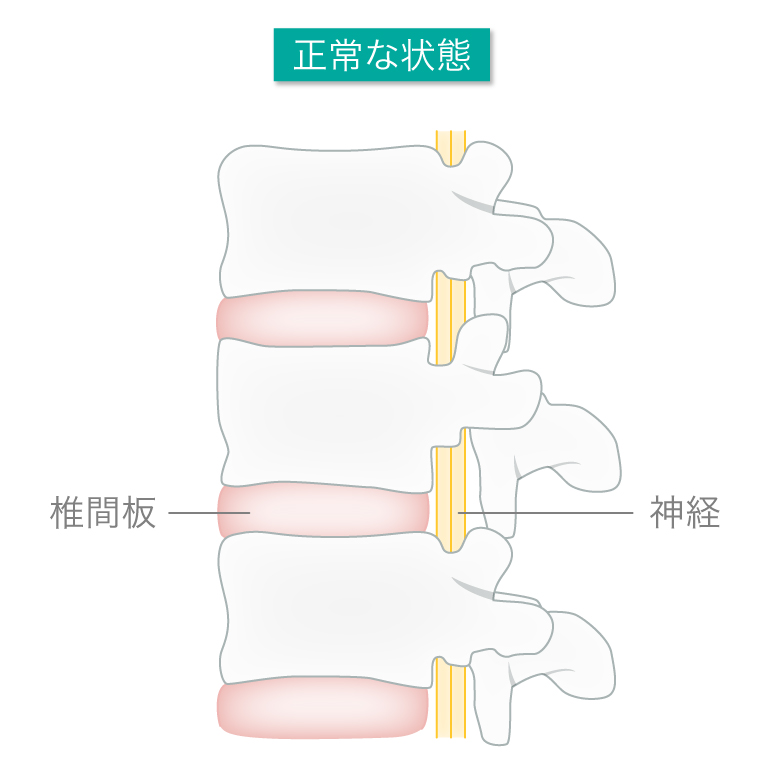

椎間板ってなんですか?

「椎間板」とは、わたしたちの身体を支える首から腰までの骨を連結させている「骨と骨の間の組織」のことを言います。椎間板の中心には核と呼ばれるゲル状の「髄核(ずいかく)」と髄核を取り囲む柔らかい組織の「線維輪(せんいりん)」の二重構造になっています。

椎間板はクッションのような働きをしていて、背骨にかかる圧力を分散させ、衝撃を吸収。さらに上下の骨を支えたり、お辞儀や体をひねったりという身体の動きに関与している場所です。